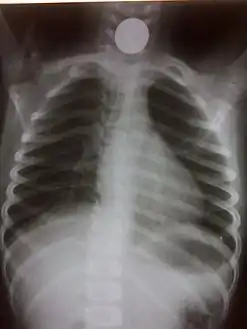

Chest radiograph showing a Venezuelan 25 cent coin lodged in the upper esophagus of a 9-year-old girl.